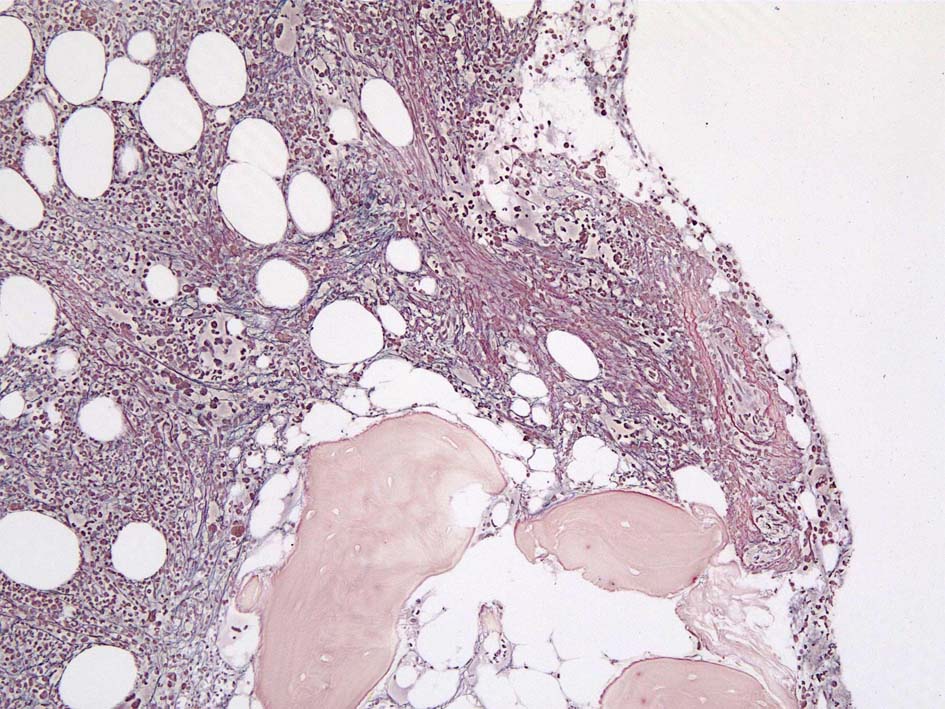

Case02; Meylofibrosis, overt fibrosis

77year-old female. 40歳時polycythemia veraと診断されていた.

黒染する弾性線維の増生のほか, 赤く染まる膠原線維の増生が確認される. MF-2 fibrosis. 鍍銀染色の核染色をすると膠原線維の赤染がわからなくなるので行わない.